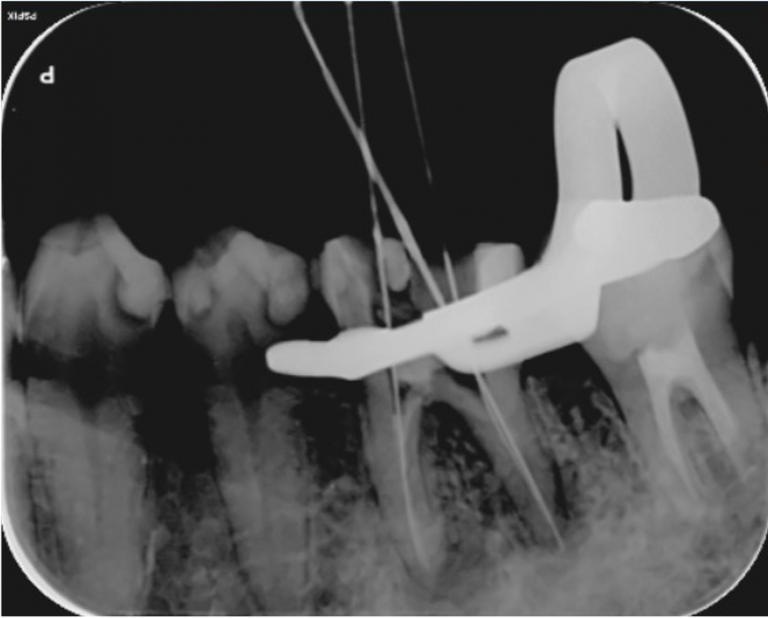

歯の根の治療中のレントゲン写真です。

歯の根の中を清掃する器具を入れています。根の中のばい菌を除去してきれいにしています。